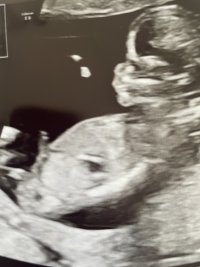

Har sett på utallige ultralydbilder til nub-tolkning, og likevel aner jeg ikke helt hva jeg skal se etter :wacky: Noen som kan tenke seg å tolke? Disse er tatt 14+4

Selv synes jeg det ser ut som jente, samtidig så så vi et tverrsnitt av baby og da var det noe langt med noe som lignet testikler mellom bena (har ikke bilde av det)

Dette er en jente. Jeg har zoomet inn på nederste bilde og man ser tydelig at det er kjønnslepper og klitoris. Pung utvikler seg ikke før i uke 15-16 så det må ha vært noe annet dere har sett.